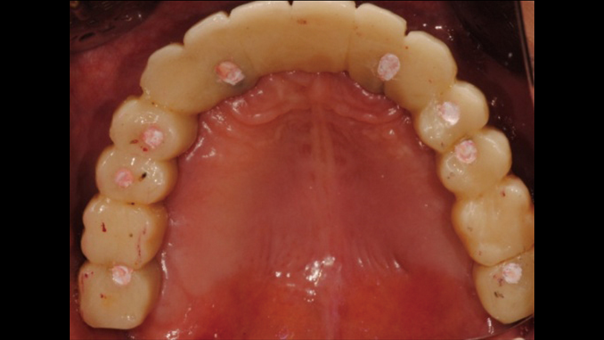

Clinical case: A Full transition from natural teeth to all-on-6 bridges

with AnyRidge implants

- Courtesy of Dr. Rabih Abi Nader, UAE -

Keywords

Full-mouth rehabilitation, minimal layering, Zirconia, all-on-6, life changing result, edentulous ,Dr. Rabih Abi Nader, AnyRidge

Products:

AnyRidge implant system